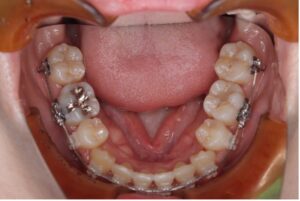

上の歯は裏側、下の歯は表側に装置をつけるワイヤー矯正です。

笑ったときに見えやすい上の歯は裏側にすることで見た目への影響を抑えることができます。

上の裏側についてる装置が舌に触れるため慣れるまで発音に違和感はありますが、フルリンガル(上下裏側)に比べると影響は少ないです。

〈メリット〉

・正面から見た時に装置が目立ちにくい

・フルリンガルより費用が抑えられる

・舌への違和感が比較的少ない

〈デメリット〉

・下の歯の装置は見える

・装置装着後は違和感を感じやすい